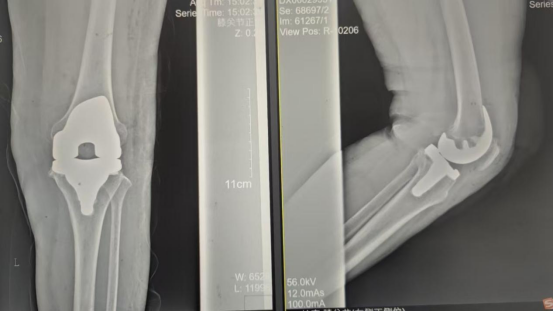

手術(shù)當(dāng)天張女士懷著忐忑的心情進(jìn)入手術(shù)室,然而伴隨著麻醉醫(yī)師的和藹交談和手術(shù)護(hù)士的溫馨叮嚀,在不知不覺中慢慢睡著,手術(shù)非常順利。術(shù)后經(jīng)醫(yī)護(hù)人員的精心治療與護(hù)理,張女士康復(fù)出院,最終解決了10余年的病痛。

術(shù)后影像資料